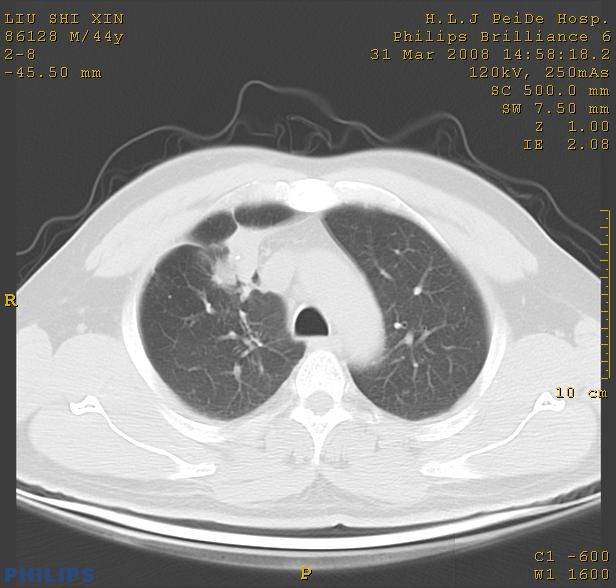

标题: CT13096:请分析胸膜下结节的影像基础是什么 有病理结果 [打印本页]

标题: CT13096:请分析胸膜下结节的影像基础是什么 有病理结果

瘢痕挛缩,胸膜牵拉,血管纠集扭曲,上叶前段支气管显示欠清,周围散在斑片影,以纵隔旁肺癌可能性大。请穿刺检查。

中心型肺癌并阻塞性肺炎及肺内转移

中心型肺癌并阻塞性肺炎、两肺及胸膜多发转移。

结节灶与血管末梢相通象转移灶;小三角状尖部有纤维索是胸膜拉扯征;纵隔旁大片实性影有点状钙化;周围有名显纤维瘢痕征可考虑瘢痕癌

本病例有病理结果是,鳞状上皮癌,胸膜下结节影病现诊断的肿大淋巴结,谢谢大家分析,请问胸膜下结节是肿大淋巴结怎么解释